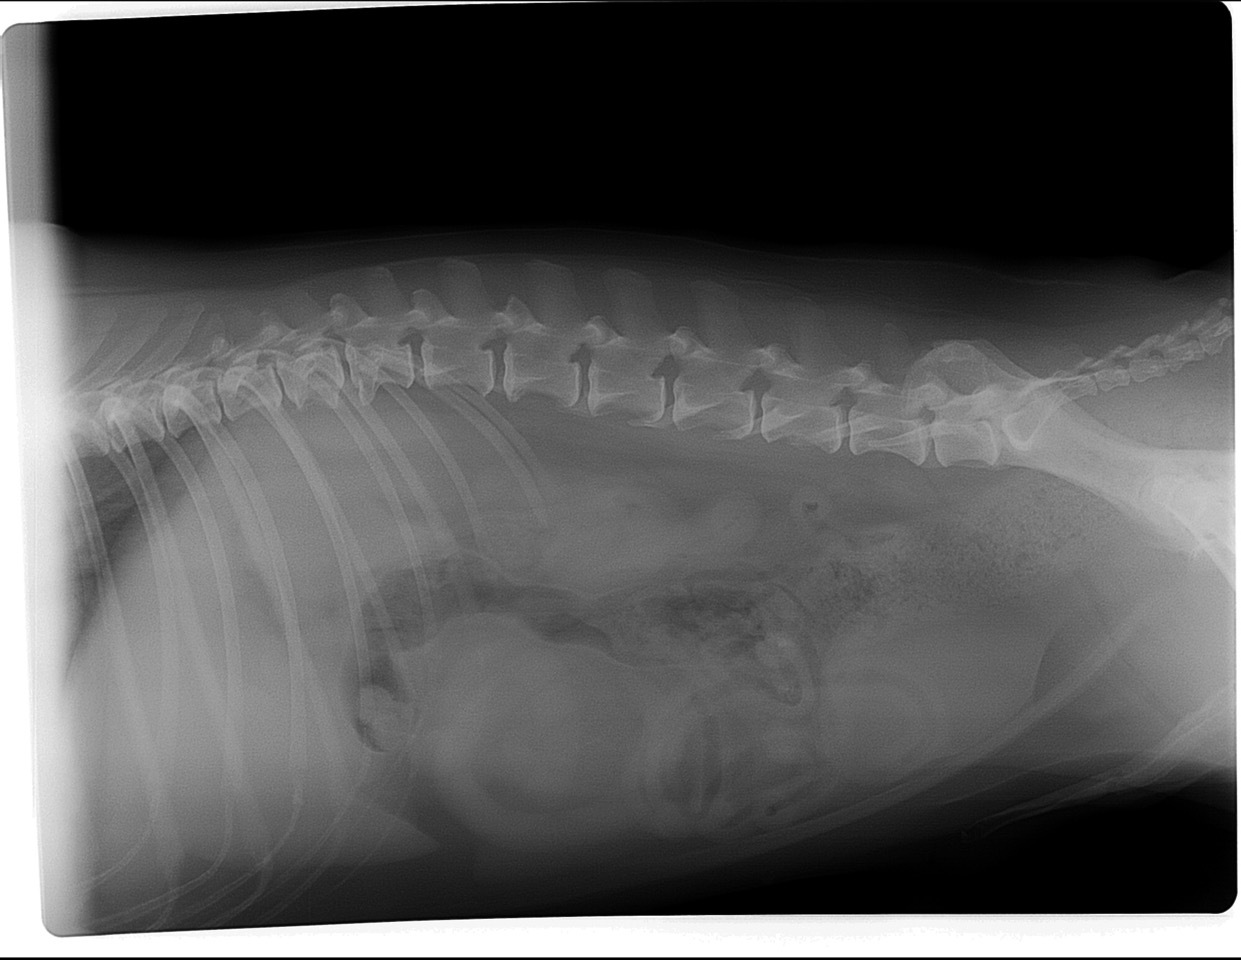

Die Röntgenaufnahmen des Haustierarztes vom linken Knie sowie des Knies und der Hüfte zeigen einen alten Kreuzbandriss (KBR) mit bereits hochgradiger Arthrose des Kniegelenks. Die Knie-Mechanik wird durch die Arthrose vermutlich mehr beeinträchtigt als durch den KBR. Weitere Röntgenbilder liegen nicht vor. Da Lea zudem sehr auffällig in der Wirbelsäule ist, haben wir auch hier Röntgenbilder angefertigt. Auf diesen sind ebenfalls hochgradige Arthrosen sowie ein Bandscheibenvorfall in der hinteren Brustwirbelsäule zu sehen. Das ist wohl momentan Leas hautsächliches Problem. Bei einer Kreuzbandriss-OP mit entsprechender Lagerung und anschließender Schonhaltung wäre die Wirbelsäulen-Problematik möglicherweise noch weiter verschlechtert worden. Das hätte im schlimmsten Fall sogar zu einer vollständigen Lähmung führen können. Zudem sind die mechanischen Beeinträchtigungen im Knie durch die hochgradige Arthrose mit einer Kreuzband-OP nicht aufzulösen. Bei einer Instabilität des Kniegelenks wäre selbstverständlich eine Operation des KBR notwendig. Sofern die Stabilität des Gelenks erhalten ist, können auch durch konservative Behandlungsmethoden oft sehr erfreuliche Ergebnisse erzielt werden. In Leas Fall wäre eine Entfernung der Verkalkungen innerhalb des Gelenks empfehlenswert, sobald sie für eine OP hinreichend stabil ist, da diese „Fremdkörper“ im Gelenk immer wieder Entzündungen auslösen können.